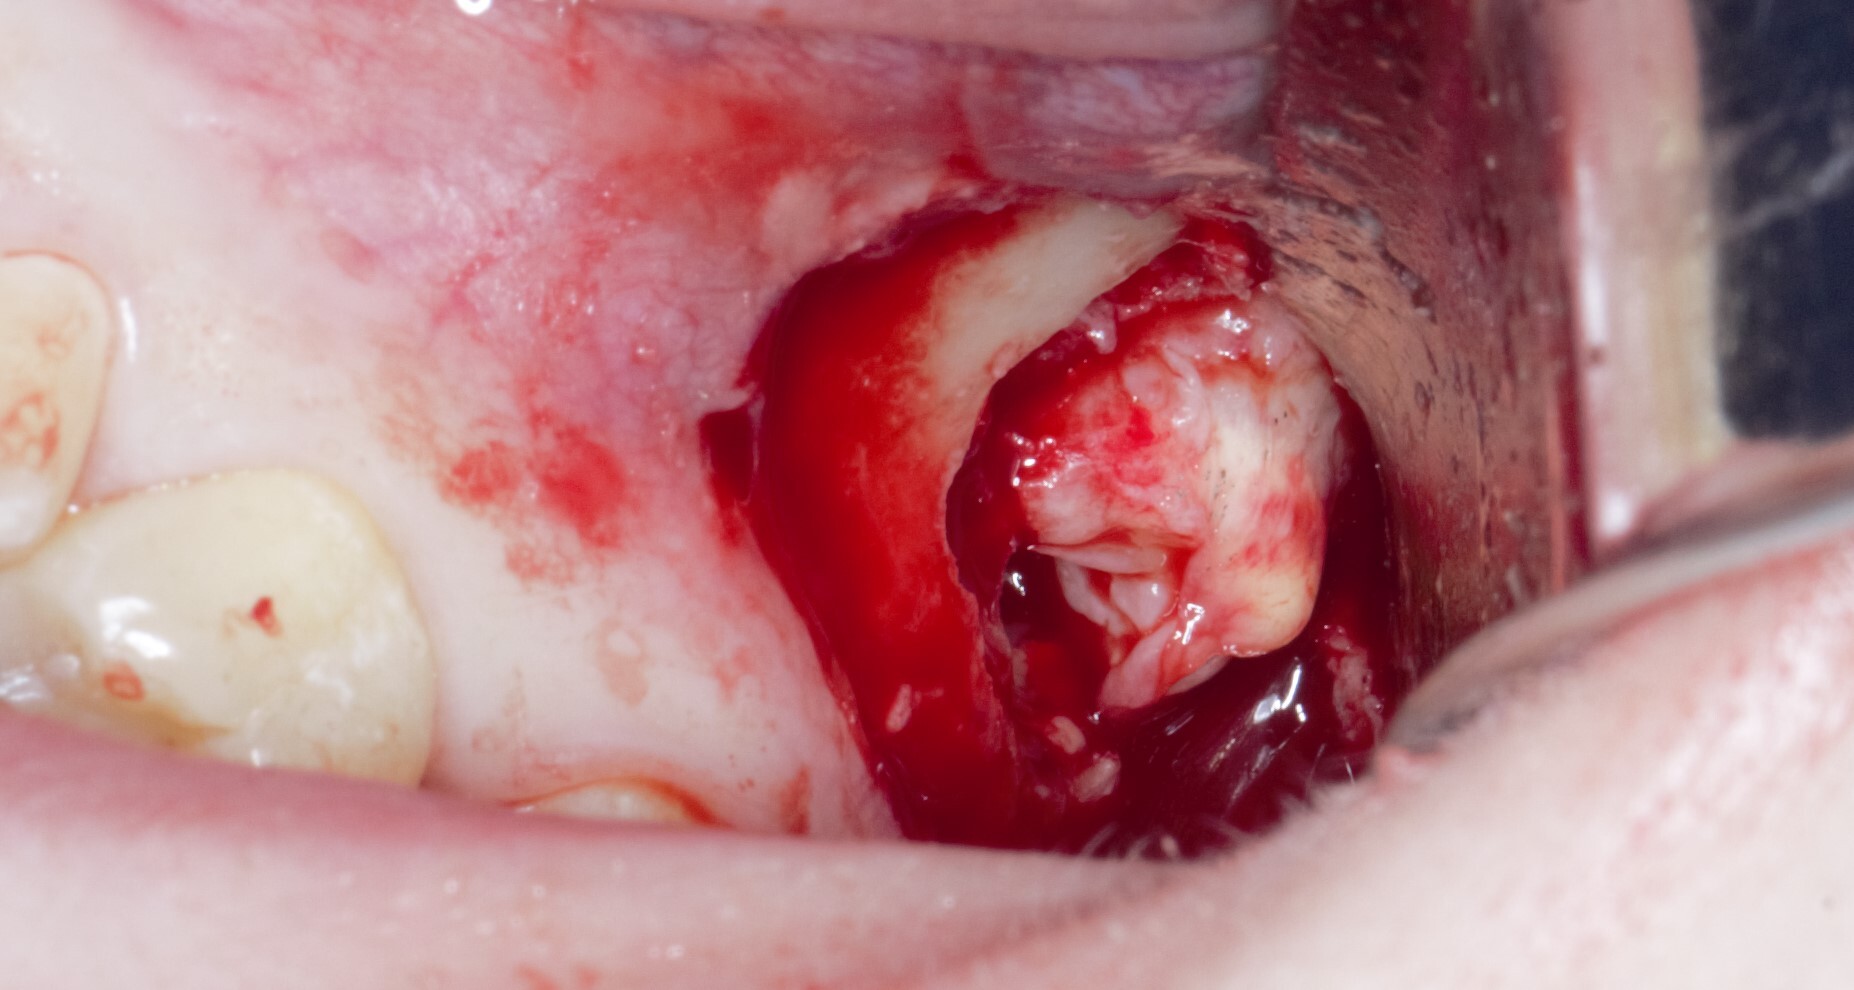

Я сделал анестезию, разрез и отслоил слизисто-надкостнечный лоскут:

Добрался до кости и при помощи специального прямого наконечника и шаровидного бора сделал окошко в проекции верхнечелюстной пазухи и удаляемого зуба мудрости:

Вооон там сверху уже можно увидеть жевательную поверхность зуба (белого цвета).

Понял, что окошко маловато. Немного «расширяемся»:

и начинаем подтягивать зуб при помощи элеватора:

Вот и он «красавчик». Берем зажим и хватаем эту мразоту за хвост, точнее за фолликул и извлекаем: